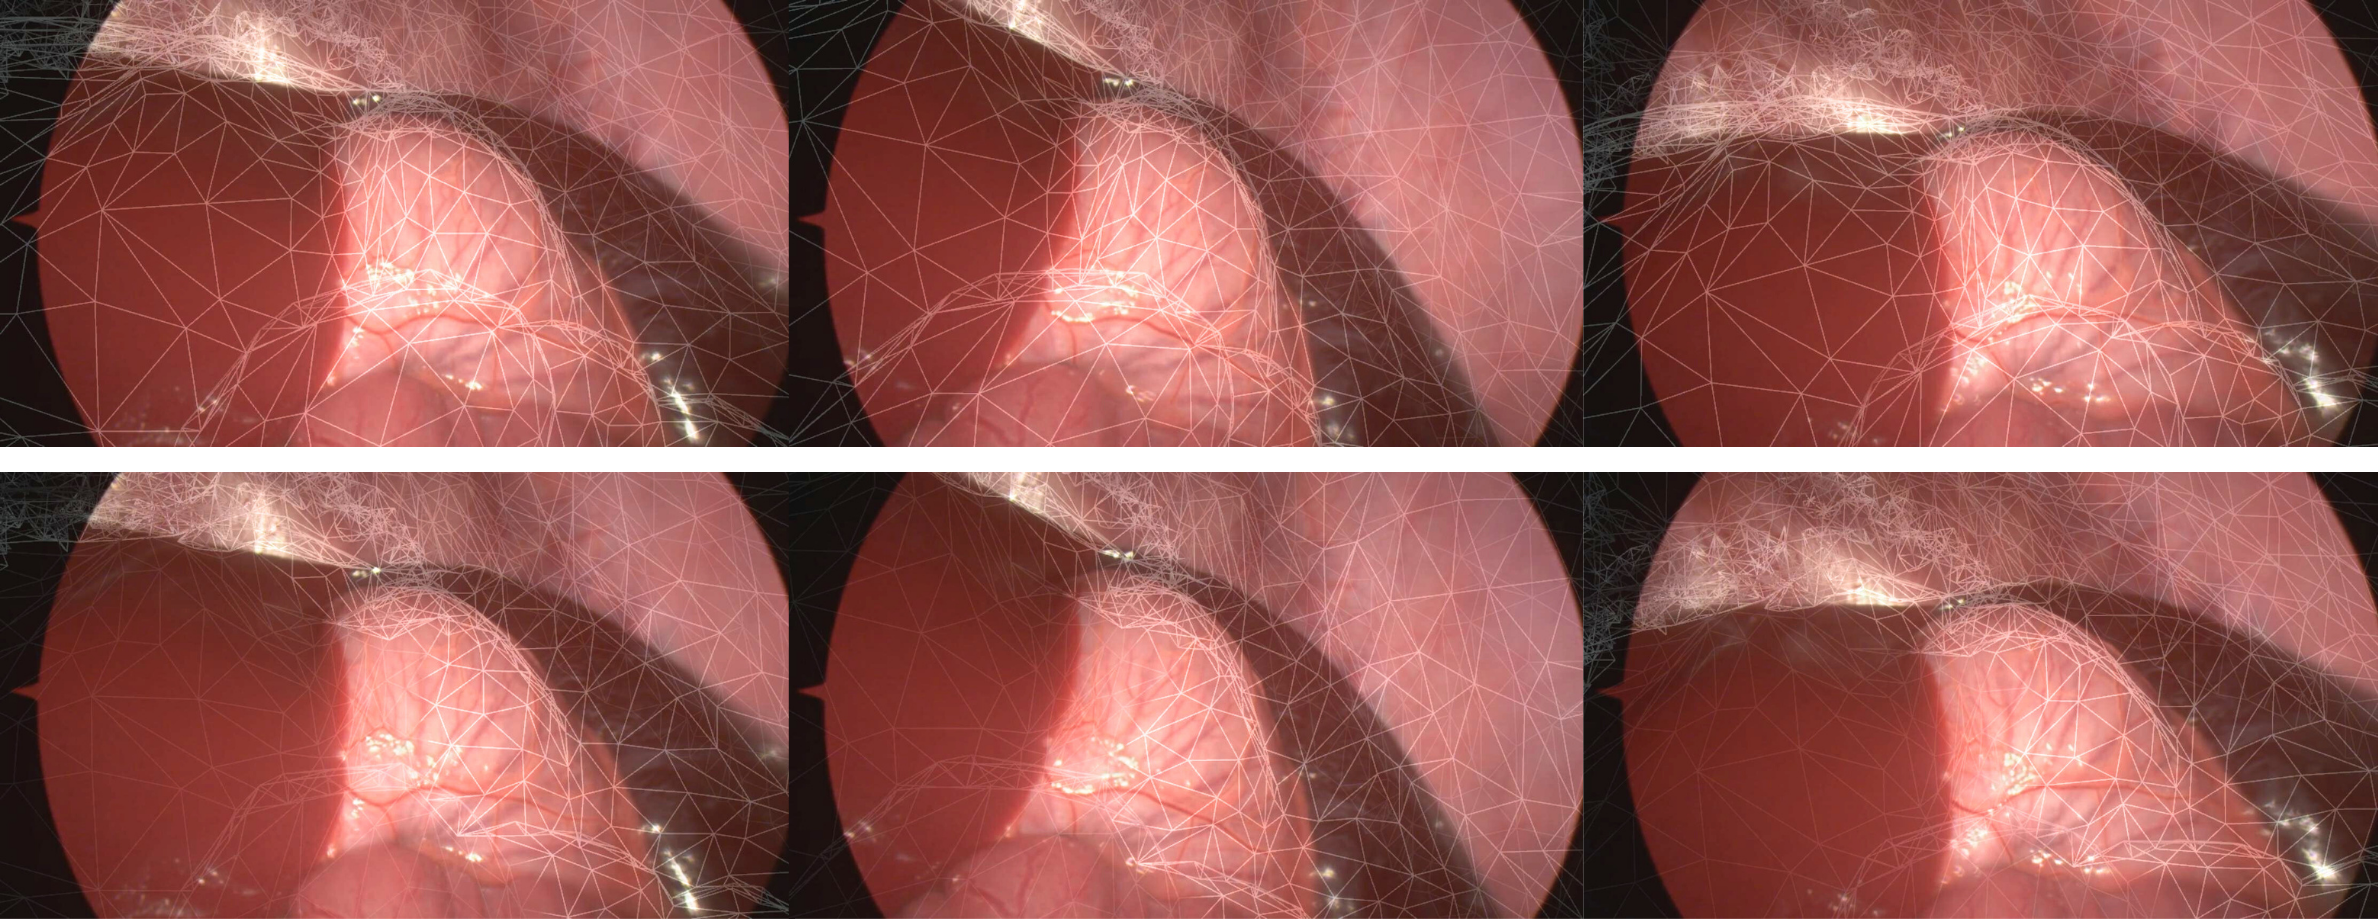

Coming from our clinical motivation, we also demonstrate potential dynamic overlays in Figure˜5 for the sequence of the second surgery, displaying breathing motion. The overlays improve over the initial rigid registration, demonstrating the method’s ability to pick up on subtle deformations.

Refer to caption

Figure 5: Top row: overlays based on rigid registration. Bottom row: deformed overlays with our method. Deformations are subtle (see video).